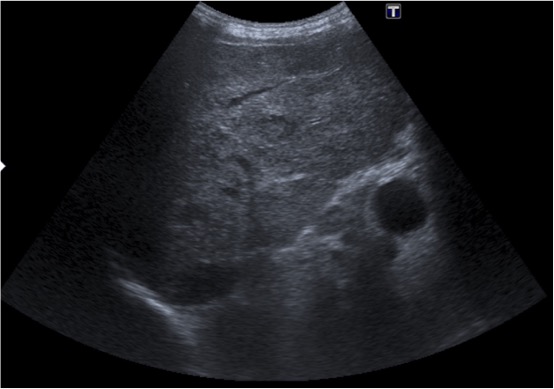

Tras el tratamiento de la recidiva y nefrostomía para la hidroureteronefrosis, vuelve acudir al hospital a los 9 meses por episodio de dolor en FD y malestar general. Se realiza una ecografía de urgencias.